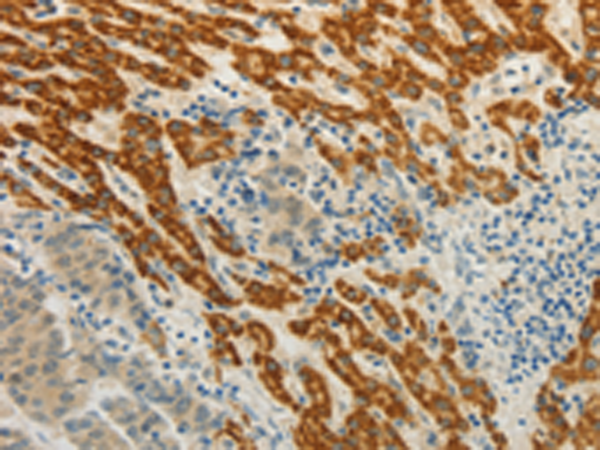

分类: 科研抗体货号: P03900别名: EPH, EPHT, EPHT1应用: IHC反应种属: Human, Mouse